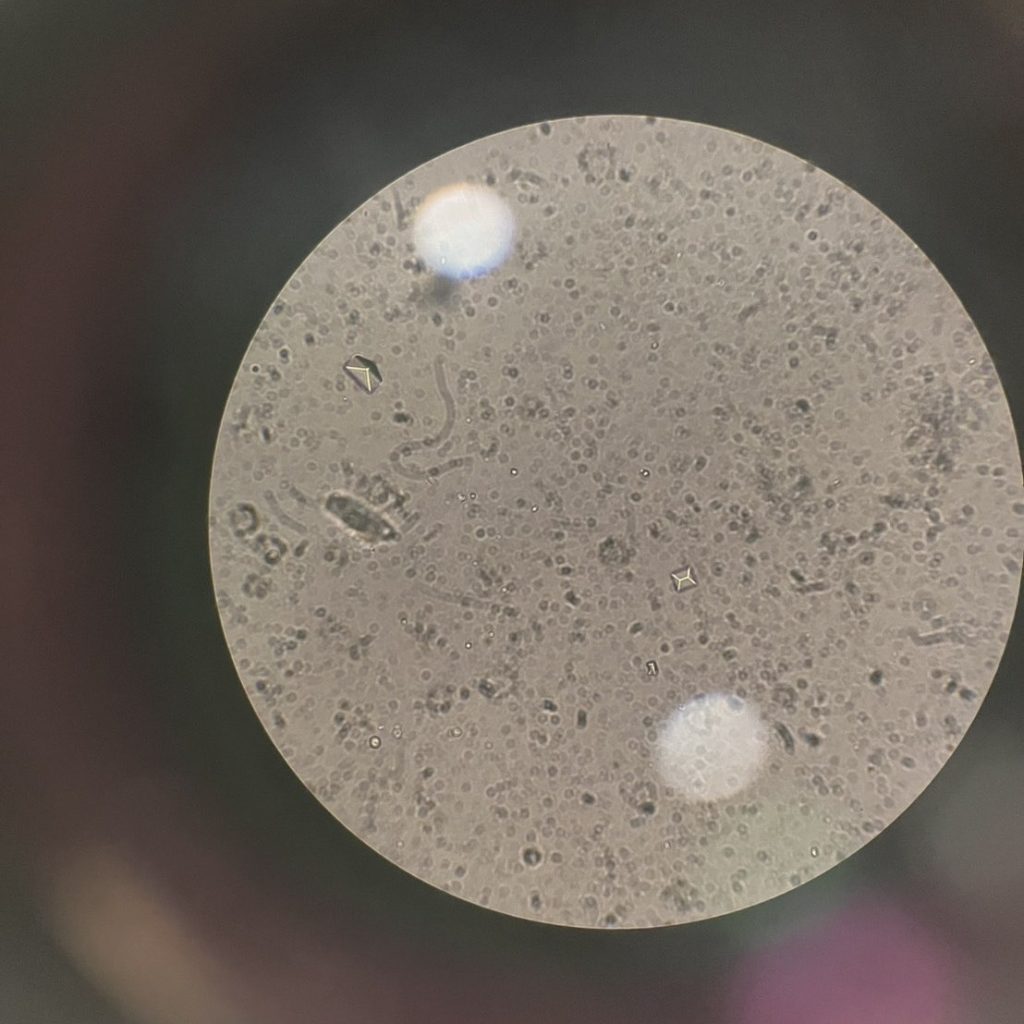

- 尿液檢查:測酸鹼值、比重,觀察蛋白尿、血尿、細菌與結晶。

尿液檢查顯示:

- 尿液 pH 值 8.0(偏鹼性)

- 可見球菌與大量鳥糞石(struvite)結晶

臨床檢查:X光下有一結石影像,超音波下也有結石影像。PH7.5,鏡下可見struvite結晶 。